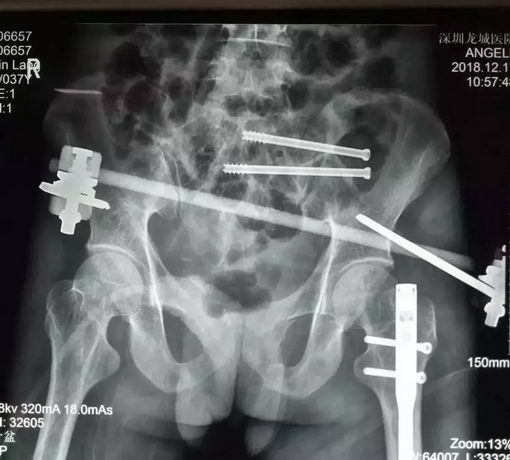

由于覃先生病情非常危重,医院立即开启绿色通道,紧急安排住进骨科抢救室。根据检查结果初步诊断覃先生为重症多发伤。骨科博士汪金平详细介绍说,患者的主要诊断包括:① 创伤性休克;② 骨盆多发不稳定骨折:左侧骶骨粉碎性骨折、右侧耻骨上下支粉碎性骨折;③ 左侧股骨干骨折;④ 右侧踝关节骨折;⑤ 急性失血性贫血等情况。

影像资料显示,患者骶1椎存在发育畸形,这种骶骨畸形增加了实施骶髂螺钉固定的风险,因为骶骨里和周围有大量的神经和血管呈网状分布,手术中一点偏差可能造成无法挽回的严重后果,轻者损伤神经造成患者瘸腿,重者损伤血管导致大出血而造成患者死亡。

12月14日,在患者伤后第三天,由博士带领团队为患者施行了透视下实施经皮骶髂螺钉固定术,首先闭合复位骨盆骨折成功,即刻经皮置钉完成前环外固定架固定术以稳定骨盆。然后顺利地经骶1椎和骶2椎各置入一枚骶髂螺钉固定,至此骨盆的前后环均获得牢固固定。手术历时近2小时,所有切口加起来的总长度不超过5cm,手术中出血不到10毫升。术后复查显示骨折复位和内固定位置都很好,医生评估预计手术后三个月可以正常行走。